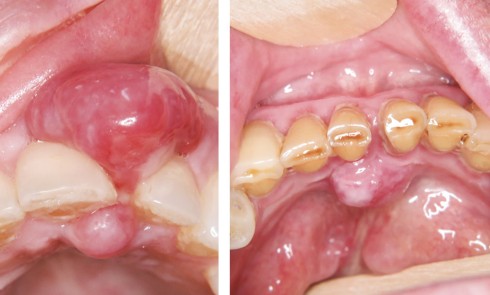

Article réservé à nos abonnés Nodules gingivaux : ne pas oublier l’examen anatomopathologique

CAS 1 Motif de la consultation Patiente de 51 ans sans antécédent médical et chirurgical adressée par son parodontiste pour une lésion...